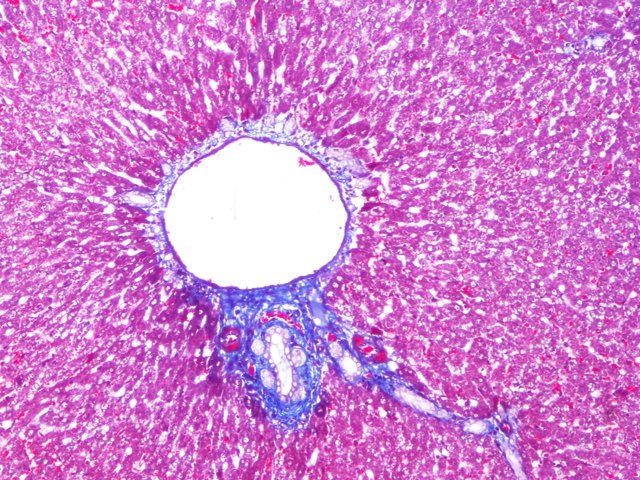

(1)可用于器官硬化性疾病的观察:如肝硬变、心肌瘢痕的观察,胶原染色更易于观察诊断。

胶原纤维呈蓝色;胞质、肌纤维、红细胞呈红色;胞核黑蓝色。

样片参考: